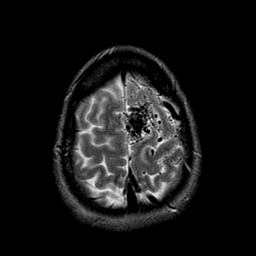

Vascular Malformation:T2-weighted MR #1 -- Slice #21

[Home][Help][Clinical] Slice 21